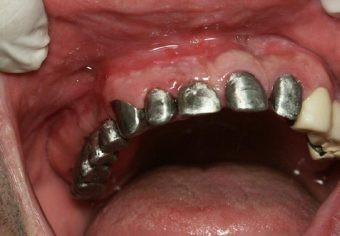

Inicial

Implantes con el Muñón Protésico